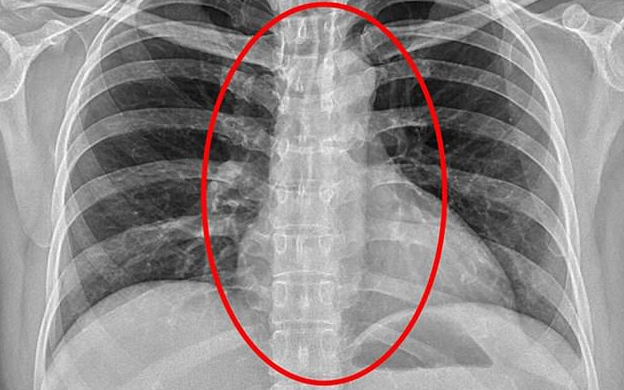

Ảnh chụp X-quang cho thấy bao cao su bị mắc kẹt trong cơ thể Đặng.

Cảnh sát sau đó phải đưa Dang tới bệnh viện để chụp X-quang. Phim chụp khiến tất cả đều bất ngờ khi dị vật gây khó thở được tìm thấy bên trong cơ thể của bệnh nhân là chiếc bao cao su.